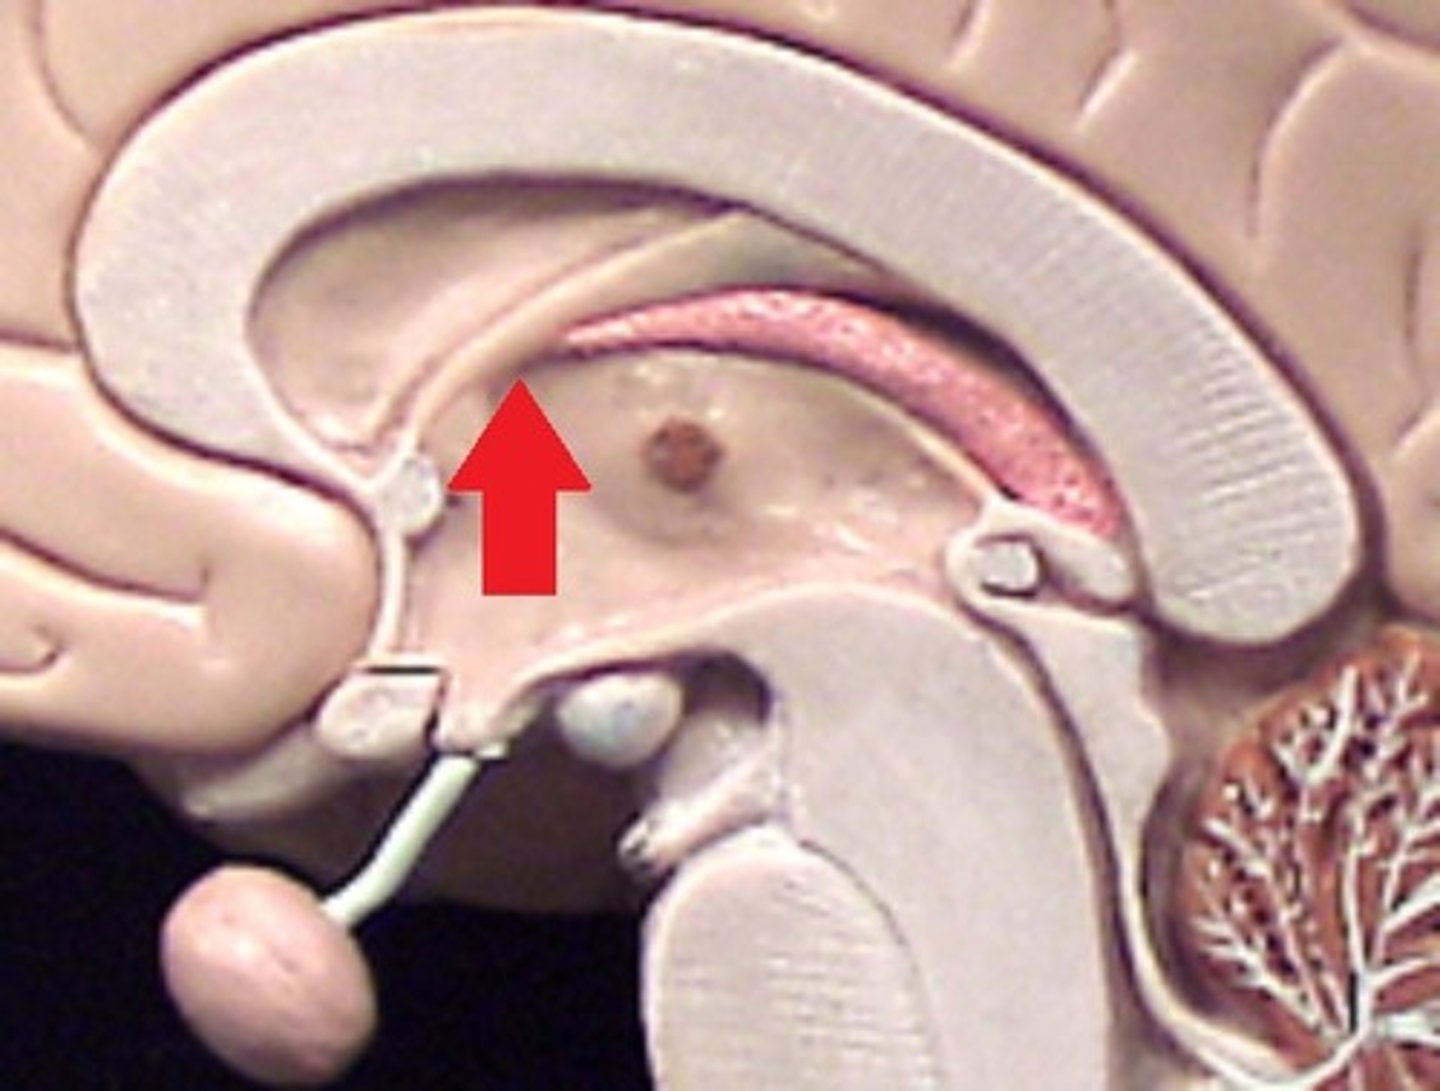

Corpus callosum

Fornix

Septum pellucidum

Pineal Gland

Intermediate mass of the thalamus

spectum pellucidum

Thalamus

Hypothalamus

Interventricular Foramen